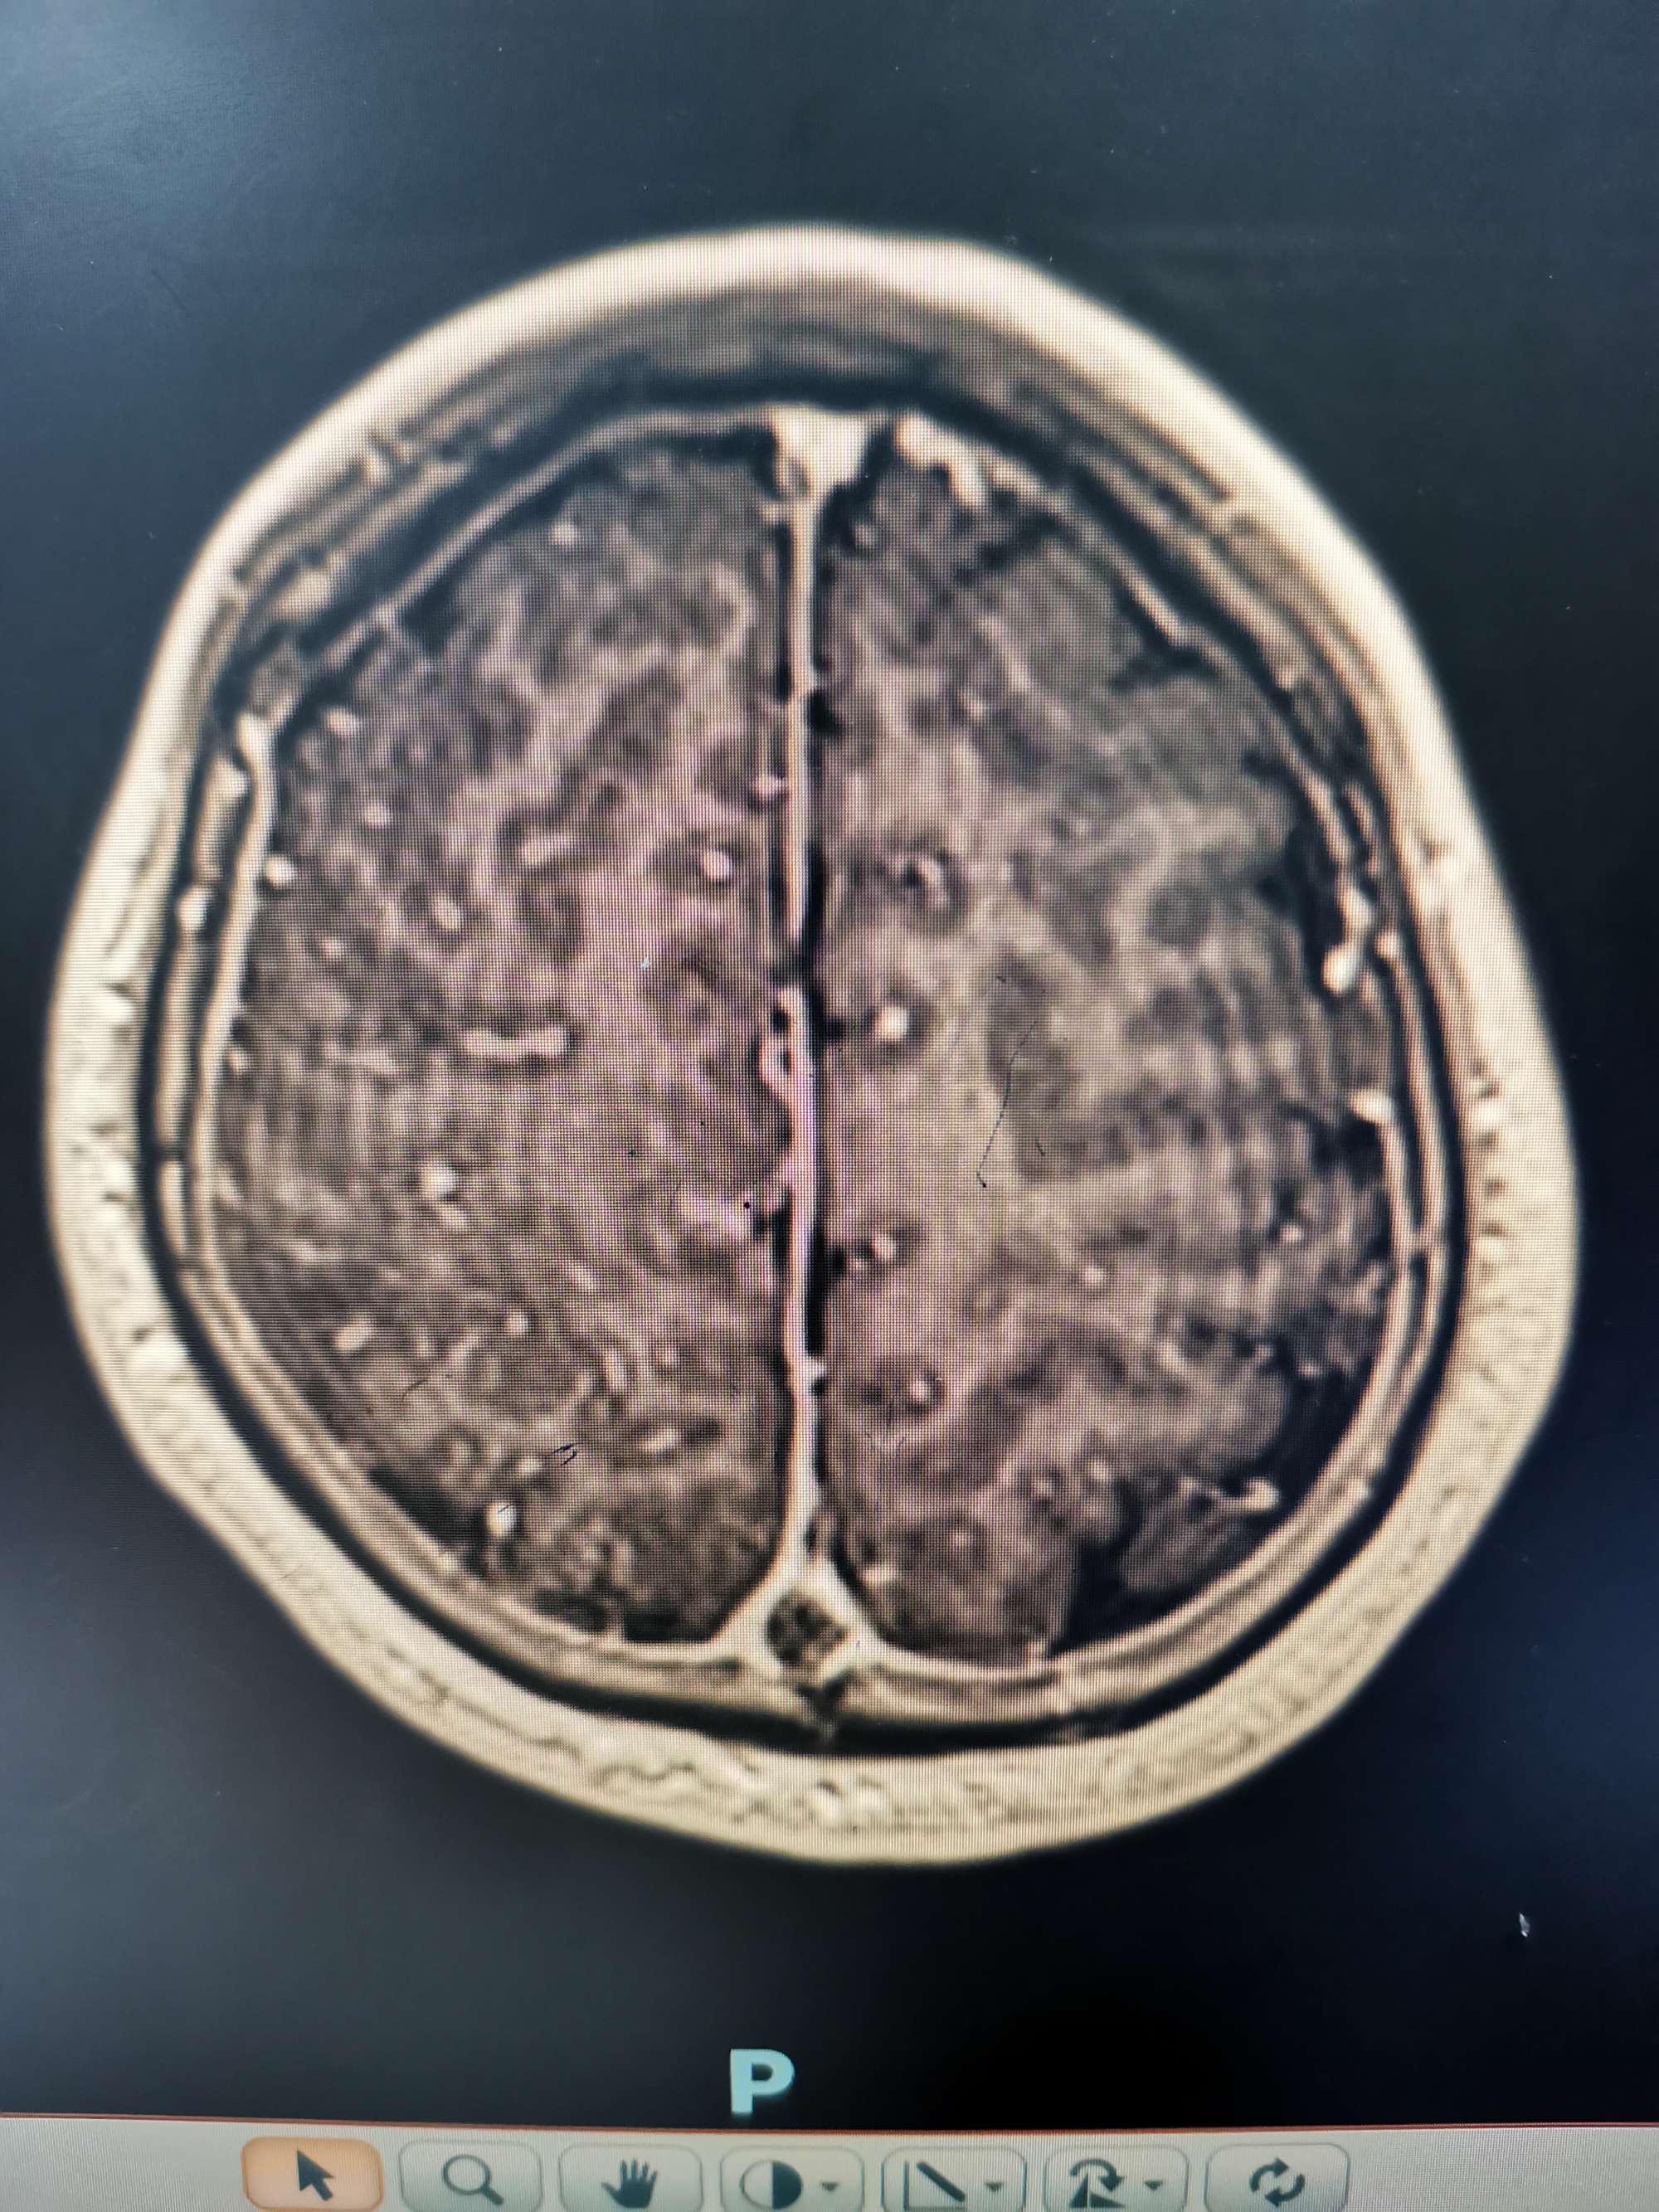

Swim技术取栓以后矢状窦起始部血流通畅

支架取出部分血栓,抽吸导管抽出大量血栓

后移中间导管,抽吸与支架相结合继续取栓。

取栓后矢状窦血流恢复通畅。

最后关头动脉短鞘竟意外从股动脉内脱出,无法行动脉造影,遗憾!只能行静脉手推造影,矢状窦恢复正向血流。

矢状窦仍有部分血栓,局部有狭窄,术后给予抗凝抗血小板治疗。术后患者意识清醒,肢体运动同术前,语言功能正常。

术后3天左下肢肌力恢复至3级。

术后一周复查MRV静脉窦通畅